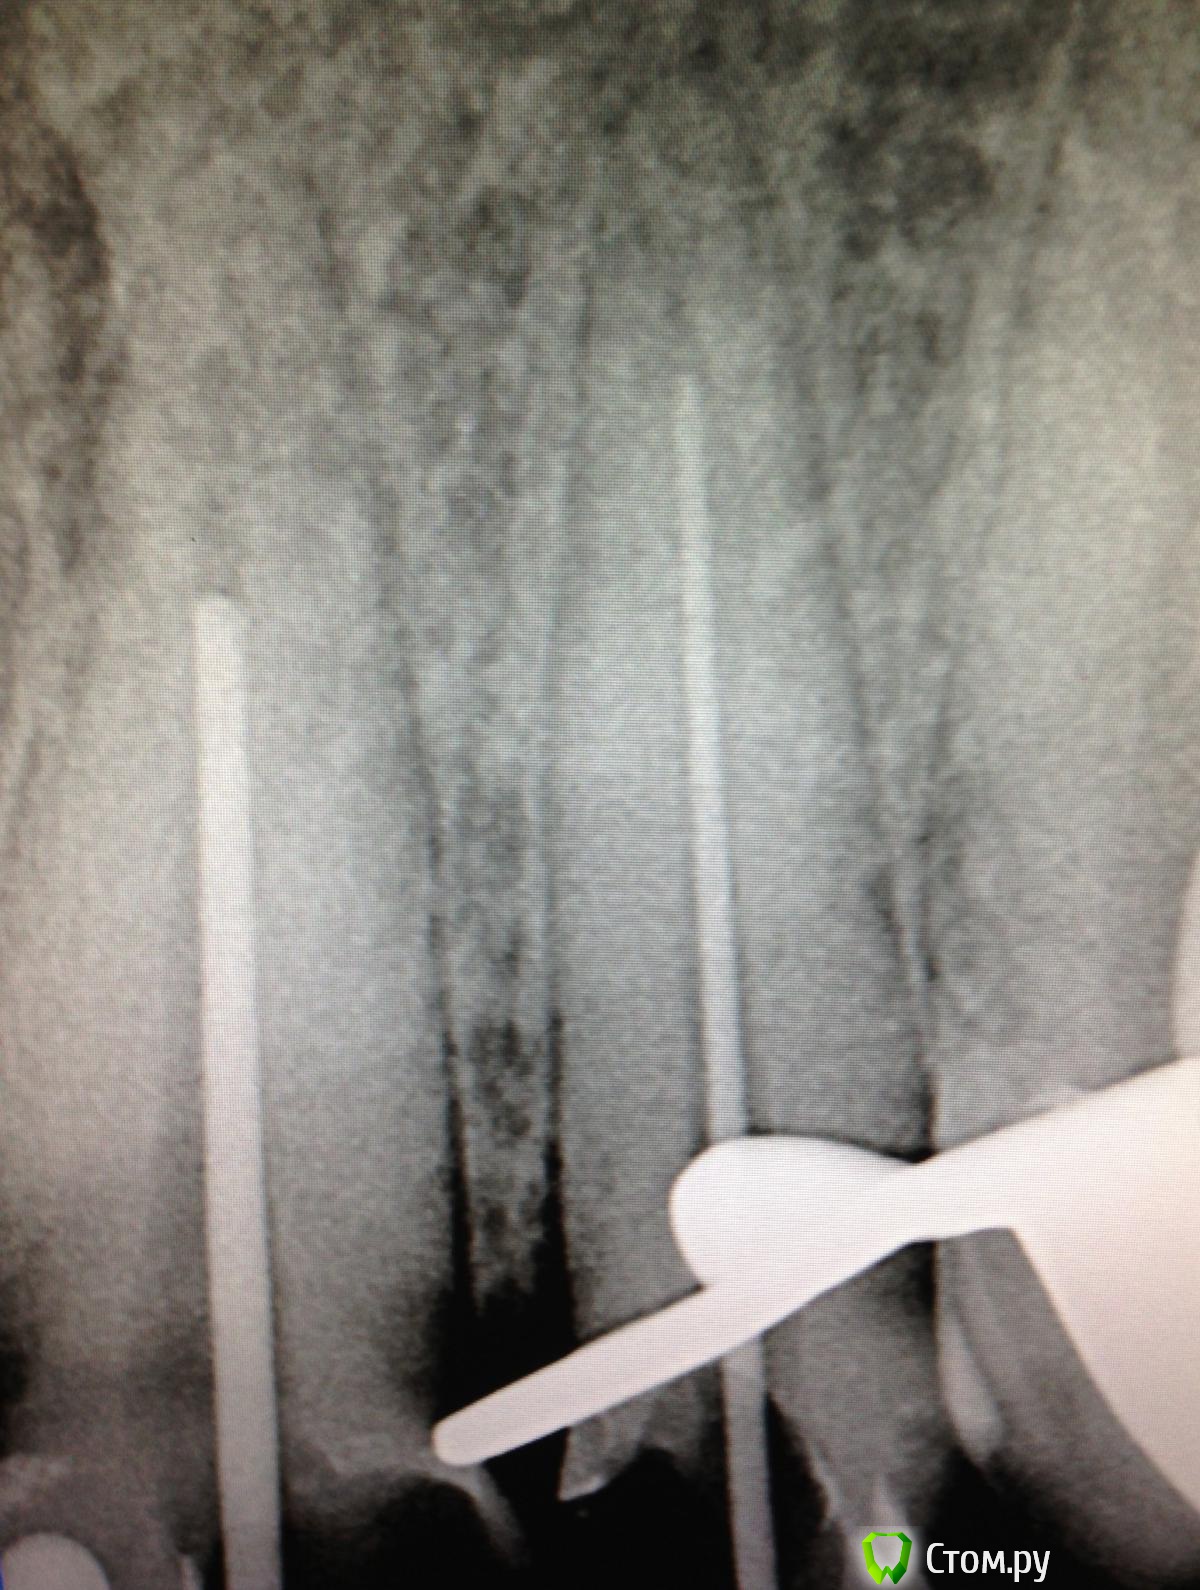

SSTi Опубликовано 19 сентября, 2014 Автор Поделиться Опубликовано 19 сентября, 2014 Новая кривулина. Начало. Попросил доктор знакомый полечить...)Неделю боли на накусывание. Иррадиируют в левый висок. Зуб 27. Внешне все ок. Маааленькая точечка в фиссуре. Шестерки нет. Делаю снимокТааааак. Позвонил доктору, сказал , как я счастлив, и приступил. Преп. Коффер. Дистально на уровне десны. Небный дистальный бугор ушел. В полости небольшой склероз. Мб сразу прошелся. Вообще без проблем. Только при хрусте файлов я чуть вспотел в области крестца))) расширились до 30.04 и дальше ручками 35.02. Мб 2 пока не нашел. Сулькус раскрыл - но там глухо. Поищем в следующий раз. Дистальный сначала только до уровня , как на снимке, потом прошел. Тоже 30.04 и 35.02. Небный- последние 3-4 мм дались с трудом. Но прошли. До 35.04 и 40.02. Мылись, сушились, кальцифицировались. Времянка. Продолжение следует 3 Ссылка на комментарий